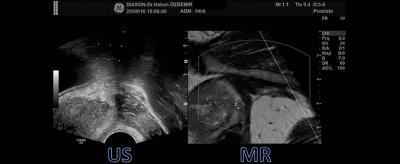

Prof.Dr. Özdemir, Türkiye'de ve dünya kullanılmaya başlayan yeni Füzyon Biyopsi tekniğinin önemine dikkat çekerek, “Standart normal biyopside şüpheli alanları göremediğimiz için hastalara yanlış tanı koyabiliriz ya da hastaya patolojide normal raporu verilmesine rağmen PSA değerleri giderek yükseliyorsa hastaya birkaç kez biyopsi yapmak durumunda kalabiliriz. Bu riskleri engellemek için son yıllarda geliştirilen en güvenilir, en yenilikçi yöntem manyetik rezonans görüntülerini kullanarak ve ultrason görüntüleri ile eşleyerek yapılan “Transrektal Ultrason-Manyetik Rezonans Füzyon Biyopsi”dir. Bu yöntem ile hastalar önce manyetik rezonans incelemelerini yaptırmaktadır. Daha sonra bu incelemede şüphelenilen alanlar varsa, bu görüntüler bu işlem için özel olarak üretilmiş olan ultrasonografi sistemlerine yüklenmektedir. Özel bilgisayar programları aracılığı ile manyetik rezonans ve ultrason görüntüleri üst üste getirilmekte ve tam doğru yerden biyopsi yapılması mümkün olmaktadır.